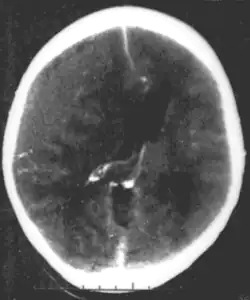

CT scan showing epidural hematoma, a type of traumatic brain injury (upper left)

Brain trauma in the developing human is a common cause (over 400,000 injuries per year in the US alone, without clear information as to how many produce developmental sequellae)[63] of neurodevelopmental syndromes. It may be subdivided into two major categories, congenital injury (including injury resulting from otherwise uncomplicated premature birth)[64] and injury occurring in infancy or childhood. Common causes of congenital injury are asphyxia (obstruction of the trachea), hypoxia (lack of oxygen to the brain), and the mechanical trauma of the birth process itself.[65]